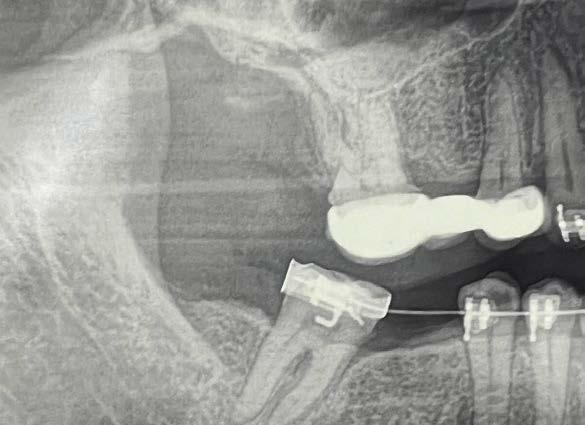

derecho (Figura 1). Especialista en endodoncia solicita cone beam en donde se visualiza lesión periapical extensa que involucra segundo y tercer molar ipsilateral y engrosamiento de la mucosa del seno maxilar sugerente de sinusitis maxilar crónica y su cercanía

con el tercer molar de dicha estructura (Figura 2).

Por lo que se propone procedimiento quirúrgico con la evidente comunicación oroantral al realizar las extracciones de los órganos dentales involucrados. Previa asepsia y antisepsia, colocación de campos estériles, extracción de segundo y tercer molar superior derecho e incisión envolvente con descarga mesial (Figura 3), rotación y afronte mediante puntos simples de la bola adiposa de Bichat para el cierre de la comunicación oroantral (Figura 4), farmacoterapia con base en amoxicilina con ácido clavulánico. Una semana después refiere no presentar rinorrea y mejoría al 100% de la obstrucción. Posterior a 6 meses de evolución clínica (Figura 5) y radiográficamente (Figura 6), no se observa comunicación oroantral o paso de líquidos de la cavidad oral a la cavidad nasal.

Figura 2. Cone Beam en corte sagital sectorial de segundo y tercer molar.

En un estudio en Latinoamérica por la doctora Novoa, se describe el aumento en los ultimos años de cone beam que tiene una calidad de imagen similar a la tomografía computarizada, con la ventaja de emitir una menor radiación, motivo por el cual fue nuestro elemento diagnóstico en este caso. Al contrario de la radiografía dental que, aunque es el examen radiológico

más usado para detectar periodontitis apical, pero al ser una imagen en 2 dimensiones donde se genera una superposición de estructuras, con una alta tasa de falsos negativos, mientras que la ortopantomografía nos permite ver la neumatización del seno, la relación de los dientes y el seno maxilar, pseudoquistes, restos radiculares y cuerpos extraños intrasinusales, pero también es una imagen en 2 dimensiones.20